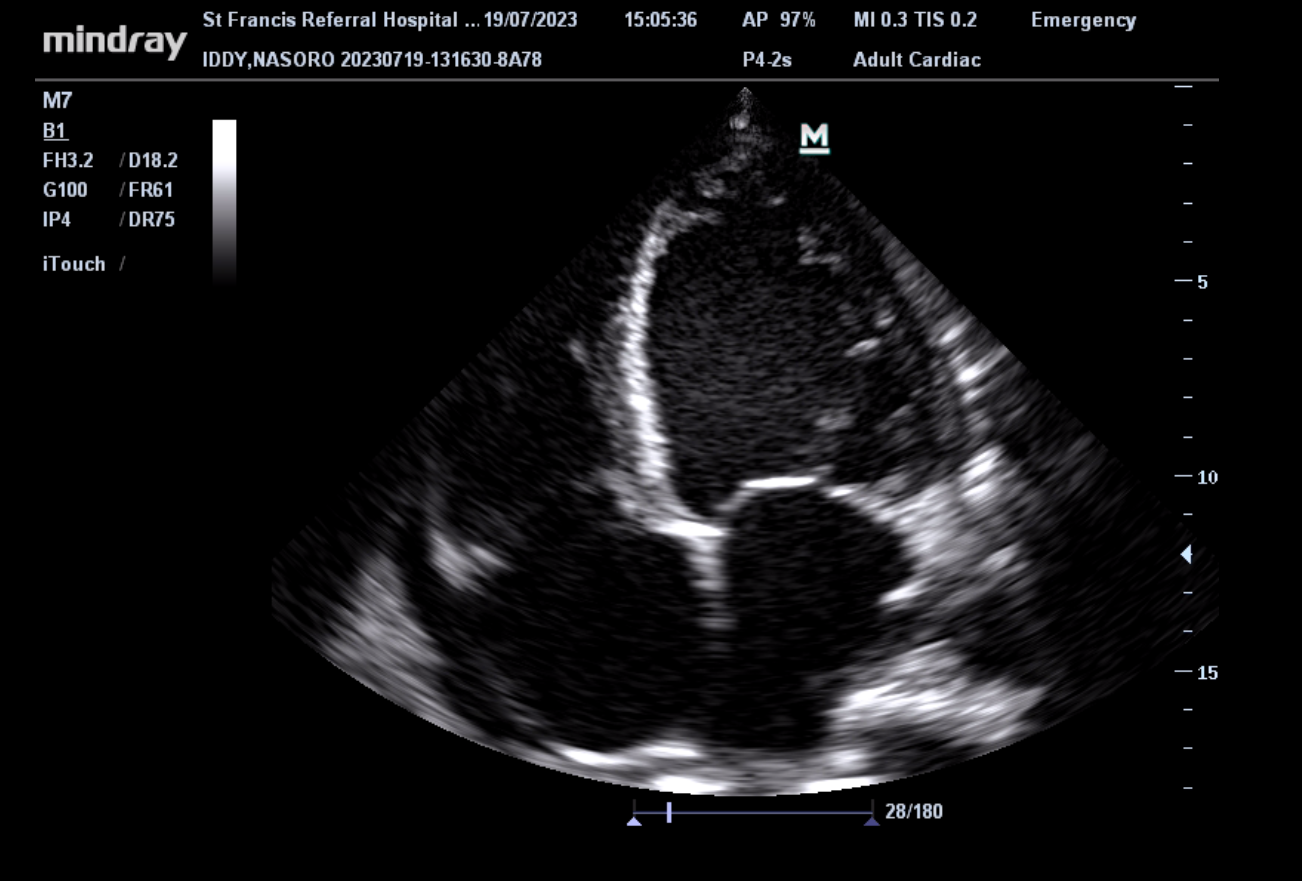

The Ifakara Health Institute (IHI), in collaboration with Swiss TPH, has launched a new interventional study evaluating the effectiveness of a drug called Sacubitril-valsartan in improving the health status of symptomatic patients with heart failure with reduced ejection fraction (HFrEF) in rural Tanzania.

The study will recruit 238 symptomatic adult patients diagnosed with HFrEF who have been on stable heart failure treatment for at least three months. The study will take place at the Heart and Lung Clinic of the St. Francis Regional Referral Hospital in Ifakara over a period of 30 months, with each participant followed for 10 months. Enrollment is expected to begin in January 2026.